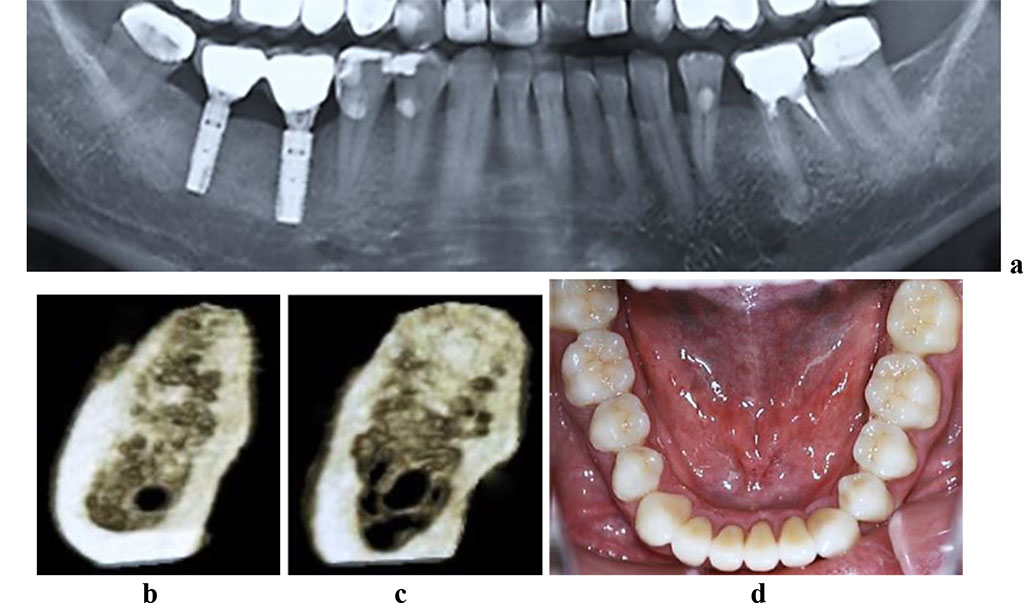

The CBCT of the cross-sectional 3D window at the area of planned dental implantation in the main group revealed minor changes in the bone tissue microarchitectonics, while the amount of bone was maintained. The 3D window of volumetric rendering mode showed that at the area of dentition defects, the cortical bone was wide and intact throughout. There were some minor qualitative changes observed in the spongy bone: the spongy bone trabeculae width and the bone trabeculae structure density were slightly reduced; there were some spots identified where the intertrabecular space was expanded; the vestibular and lingual cortical plates were intact; the trabecular structure preserved its integrity yet there was a slight change in the structure arrangement (disorientation) observed in the bone trabeculae (Fig. 6-8).

Figure 8. Patient S., 62 y.o. Diagnosis: lower jaw total adentia; Class I by Keller. Lower jaw CBCT: a – bone tissue 12 months following the installation of dental implants (panoramic reformat); b – volume rendering; 3D cross-sections at the adentia area 3.2 (c), 3.4 (d), 3.6 (е), 4.2 (f), 4.4 (g), 4.6 (h) prior to the installation of dental implants; lower dentition before (i) and after (j, k) implantological and prosthetic treatment.